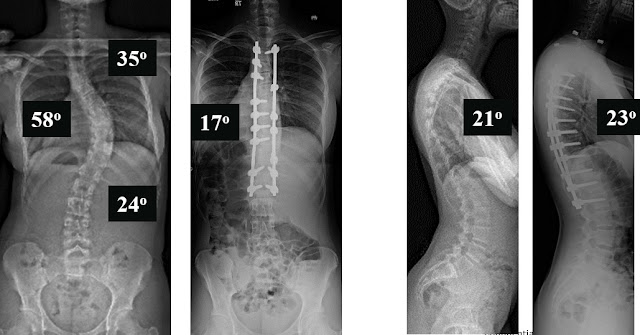

The case example is a 14 year old young lady with a 58 degree right thoracic idiopathic curve, and 35 degree proximal thoracic and 24 degree lumbar curves.

The supine side bending radiographs demonstrate the flexibility of the spine. So only the main thoracic curve of 58 degrees is what we call “structural” and the other two curves, due to the fact they bend out to be below 25 degrees, we call “nonstructural” or “compensatory”.

These postoperative radiographs are one year after surgery. The patient is nicely balanced 3-dimensionally and has nicely improved.